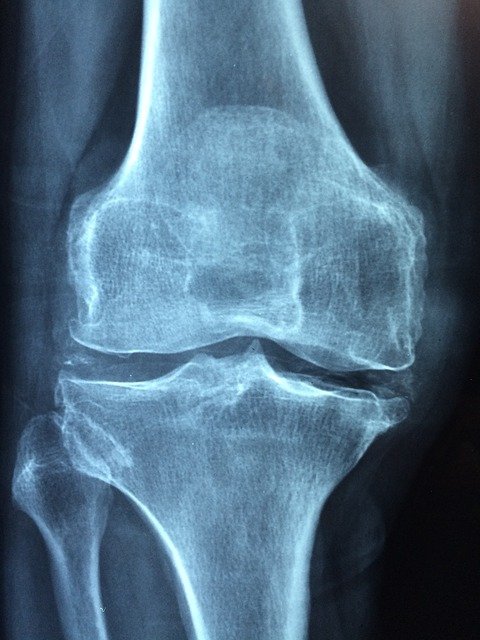

류마티스 관절염은 여러 가지 원인으로 인해서 생기는 염증성 질환으로 많이 알려져 있습니다. 류마티스 관절염은 아직 정확한 원인은 알려져 있지 않습니다. 주로 30대 이후의 여성들에게서 증상이 많이 발현됩니다. 여성들에 게서 많이 발생한다고 해서 남성이라고 류마티스 관절염에서 안전한 것은 아닙니다.

류마티스 관절염의 경우 나이 성별을 가리지 않고 전연령층에서 발생하는 질환이기 때문에 젊다고 혹은 나이가 많다고 안전한 것은 아닙니다. 우리나라에서만 류마티스 관절염으로 고생하는 사람들이 굉장히 많습니다. 현재 약 40만 명 이상의 사람들이 류마티스 관절염으로 고생하고 있고 매년 증가하는 추세이기 때문에 각별히 주의해야 하는 질환입니다.